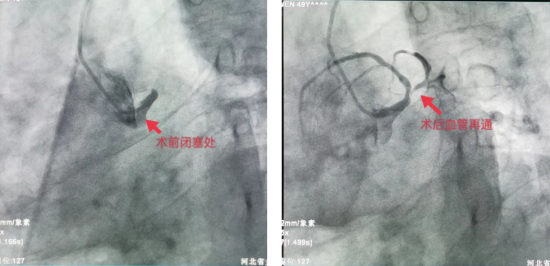

时间就是心肌,时间就是生命,医院心内科、急诊科与时间赛跑,立即启动绿色通道,确定急诊行PCI术开通冠脉闭塞血管。术中患者反复室速,烦躁,导管室团队沉着冷静,凭着扎实的基本功,操作导丝顺利通过闭塞处,球囊扩张后,血管再通,使患者转危为安。